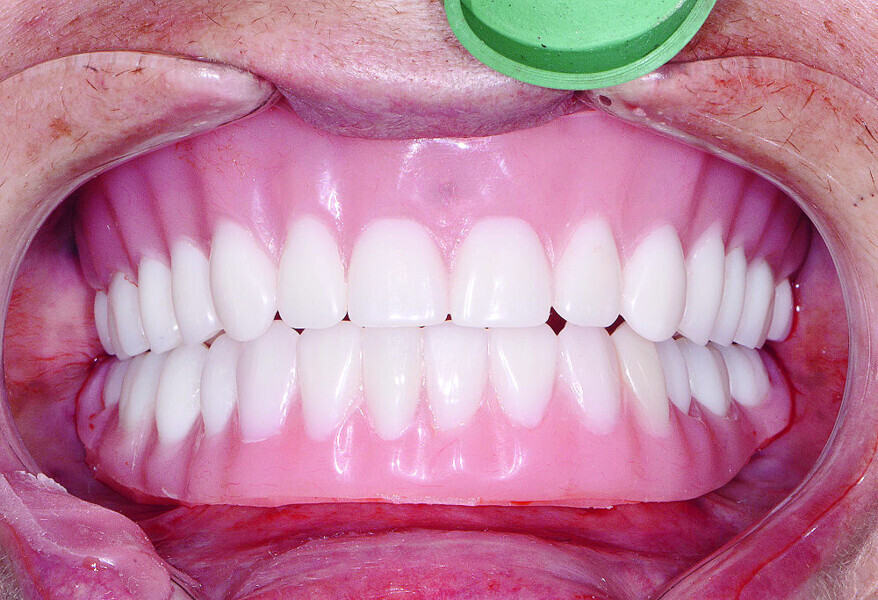

Fig 21 Vue des dents non engrenées